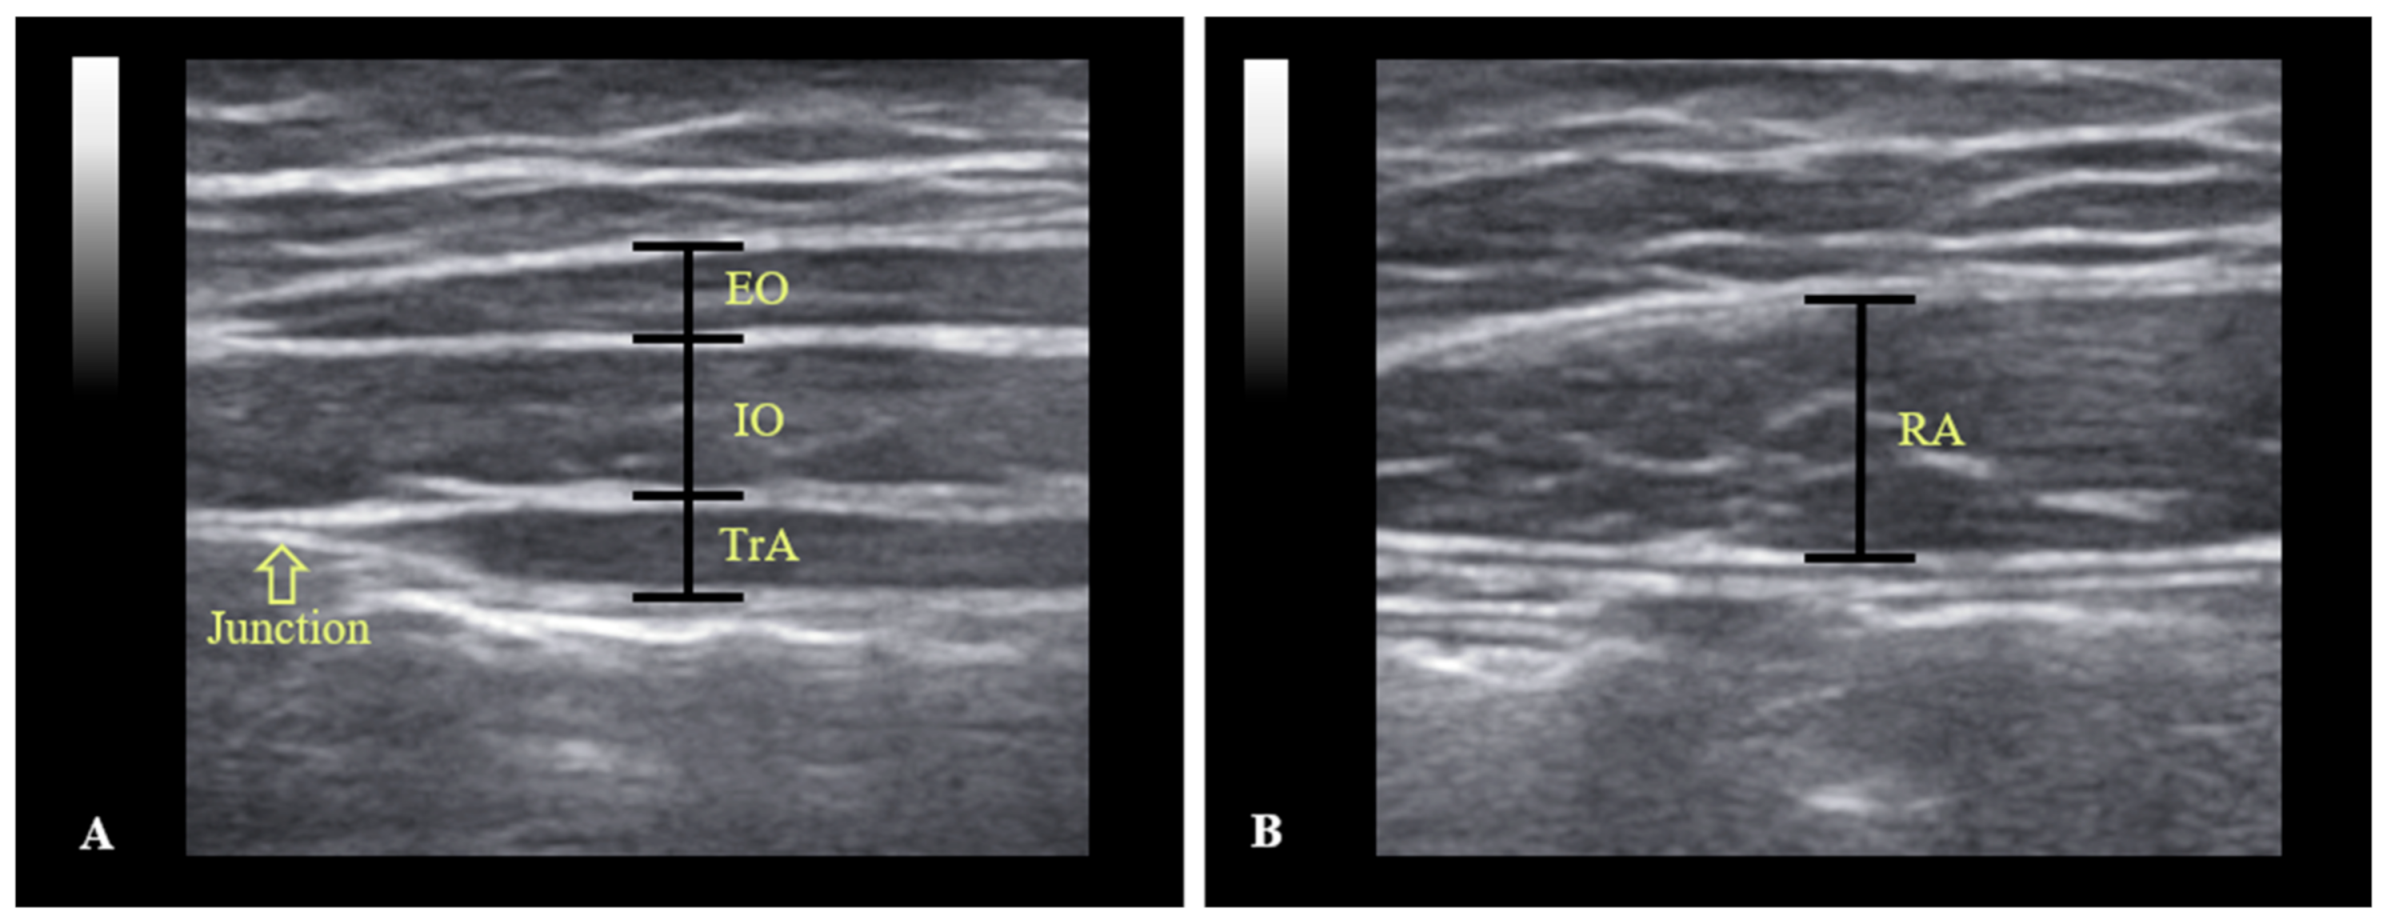

2.2. Apparatus

2.4. Data Analysis